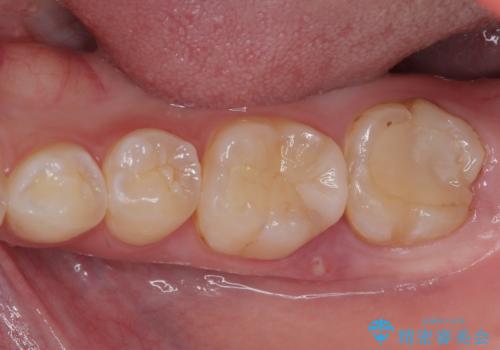

下顎大臼歯の再根管治療とオールセラミッククラウンによる補綴治療